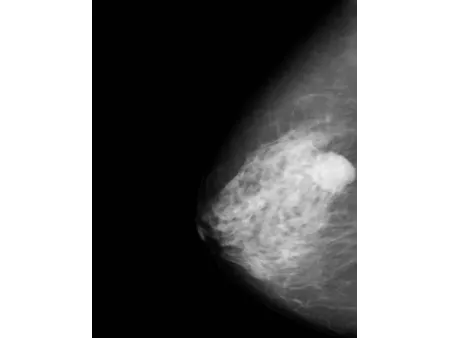

El detector plano CMOS, reconocido por su alta sensibilidad, permite obtener imágenes mamarias con gran nivel de definición. Este mamógrafo también incluye el software especializado Console, que utiliza algoritmos avanzados de posprocesamiento para mamografía, facilitando la visualización de estructuras finas y mejorando la precisión en la interpretación clínica. Con una capacidad de resolución de 60 líneas por centímetro, es capaz de detectar microcalcificaciones tan pequeñas como 0.1 mm, lo que refuerza su utilidad en programas de detección precoz de cáncer de mama y en evaluaciones clínicas más específicas.